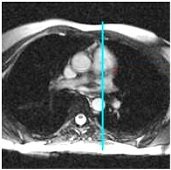

3. View the pulmonary valve image.

Figure 3. In this example, 1 = pulmonary valve